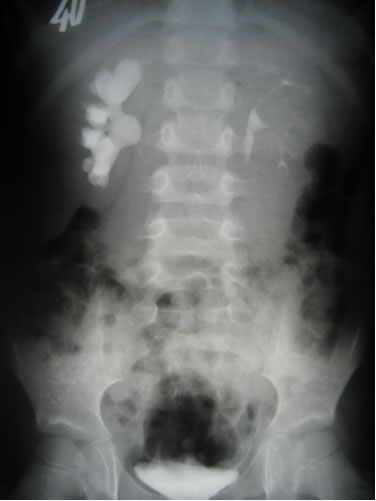

Инфравезикальная обструкция мочевого пузыря: симптомы и лечение